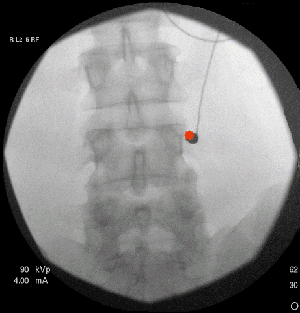

Facet Joint Injection | Barr CenterIf these techniques do not bring about the desired pain relief, we may perform a facet joint injection, which delivers a steroid or anesthetic to reduce inflammation and pain. It will also help to better diagnose the problem. We may also recommend other types of procedures such as medial branch blocks (diagnostic only) or prolotherapy.

If the facet joint injection provides temporary but not long-lasting relief, your physician may discuss the option of radiofrequency Facet Joint Injection Causes (lesioning) of the small nerves, which provide nerve impulses to the facet joints believed to cause your pain.